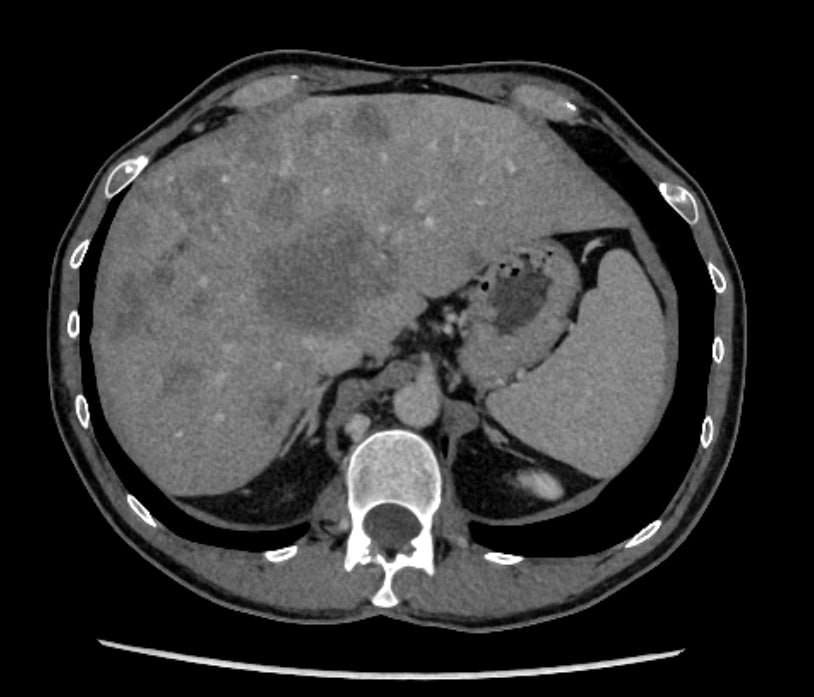

What a CT Scan with Contrast Looks Like

Here's an example of what a contrast-enhanced CT scan image looks like. This abdominal CT scan shows detailed internal structures that the contrast dye helps highlight:

This is a CT scan from Dima, OncoSteps' founder, showing extensive liver metastases from colorectal cancer after multiple rounds of chemotherapy. As someone who has personally navigated the challenges of cancer diagnosis and treatment, Dima founded OncoSteps to help others better understand their scans and make informed decisions about their care.